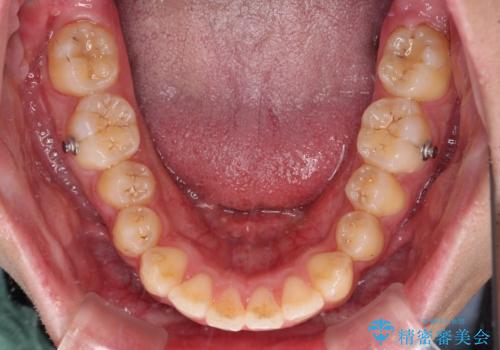

下顎の歯列は、奥歯が前方に傾斜し、前歯が上顎の歯の付け根に食い込むように内側に傾斜していました。

また、左右の犬歯の位置関係は上顎歯列が前方に位置する咬み合わせとなっており、インビザライン単体で治療するよりは、ワイヤー装置や補助装置を併用した方がより良い仕上がりになることが期待されました。

来院時は学生であったので、補助装置により上顎臼歯を後方に移動させ、下顎歯列はワイヤー装置による傾斜を改善させ、就職のタイミングでインビザラインにて仕上げていくこととしました。